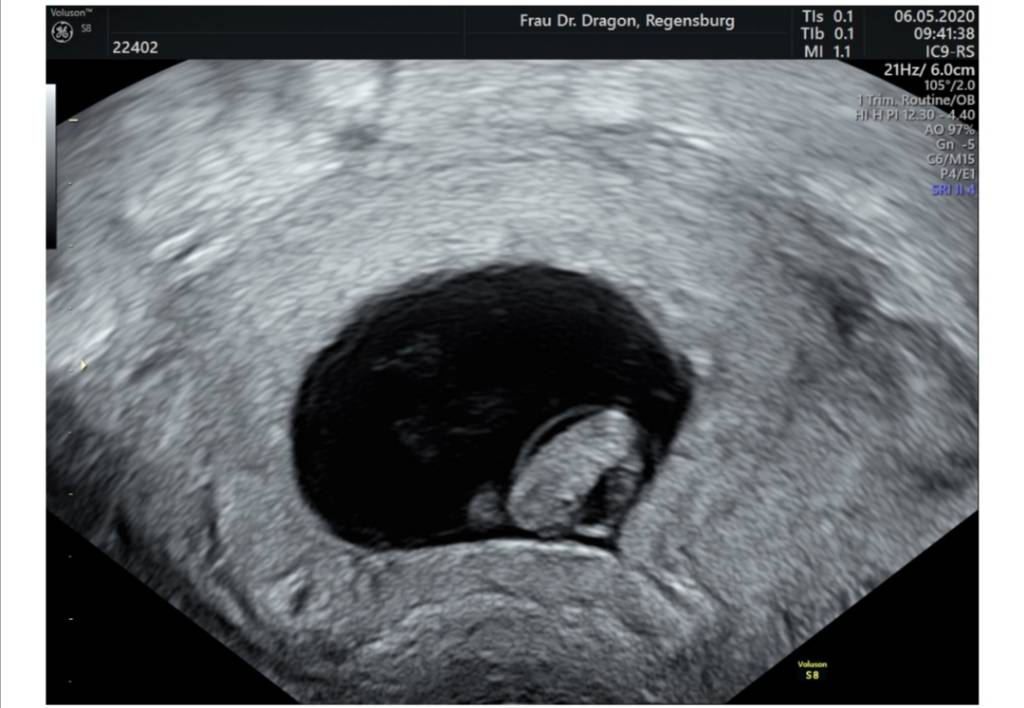

Cześć Dziewczyny. Czytam Wasze posty już od jakiegoś czasu. Nie pisałam wcześniej, ponieważ jeszcze boję się podzielić szczęściem jakie nas spotkało. Może trochę opowiem Wam moja historię. O maleństwo staramy się prawie 6 lat. Raz udało nam się zajść w ciążę ale niestety pęcherzyk ciążowy był pusty. Bardzo to przeżyliśmy. Gdy zrobiłam test nie wierzyłam, że są dwie kreski. Jestem w 7+4. Boję się bardzo, że może coś pójść nie tak. W 6+6 miałam USG lekarz na początku nie mógł znaleźć pęcherzyka strasznie się zdenerwowałam bo już raz mieliśmy taki scenariusz. Na szczęście okazało się, że jest i widać serduszko byłam szczęśliwa jak nigdy dotąd. Termin mam 26.12. Jeszcze boję się, że coś może pójść nie tak. Jednego dnia bardzo się cieszę, drugiego boję się bo może jeszcze coś pójść nie tak. Z dolegliwości mam wsumie tylko mdlosci, duży apetyt i dziwny posmak w ustach. Kolejną wizytę mam 22.05 i znów się strasznie boję. Pozdrawiam Was serdecznie.

Jest serducho [emoji3590] waliło jak oszalałe - mały człowiek we mnie mieszka [emoji7]

Słabo go trochę widać na zdjęciu przez moją tkankę tłuszczową hehe... trudno, najwyżej nie bedzie miec ladnych zdjęć w brzuchu póki co [emoji13]

Termin z USG na 31.12 - 01.01. [emoji3059] Będzie impreza [emoji4]

Za nic nie pamiętam ile ma długości...8,4 mm? Już nie słuchałam taka byłam zakręcona.